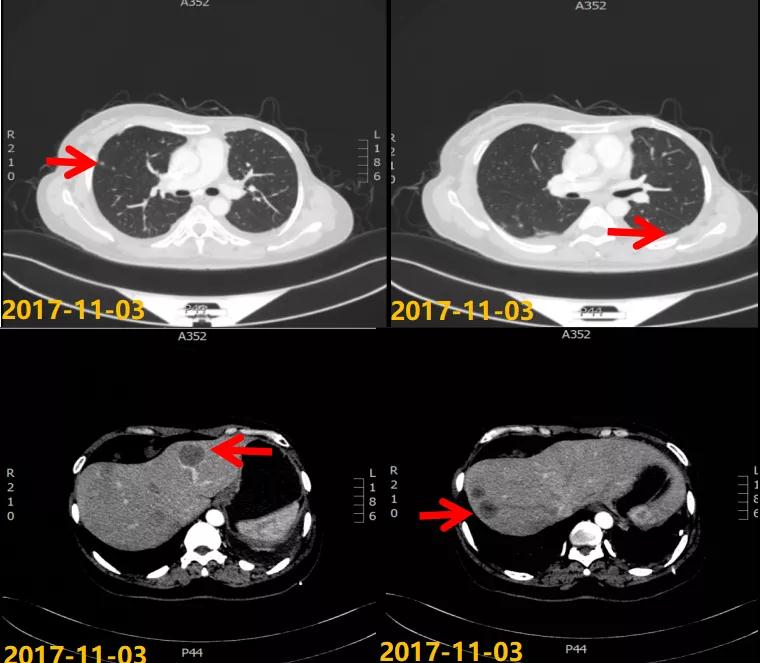

第一次病情进展: 2017-10-22患者因“气喘气憋、呼吸困难20天”就诊我院,胸水超声提示左侧大量胸腔积液,行胸水穿刺引流,查见癌细胞。2017-11-03 CT:两肺多发结节,考虑转移瘤;左侧胸膜斑块状增厚,提示胸膜转移;肝脏多发转移瘤。进一步行肝脏肿块穿刺活检,病理:ER(2+,90%),PR(3+,80%),HER2(2+),Ki-67(+,40%),FISH检测:未观测到基因扩增。